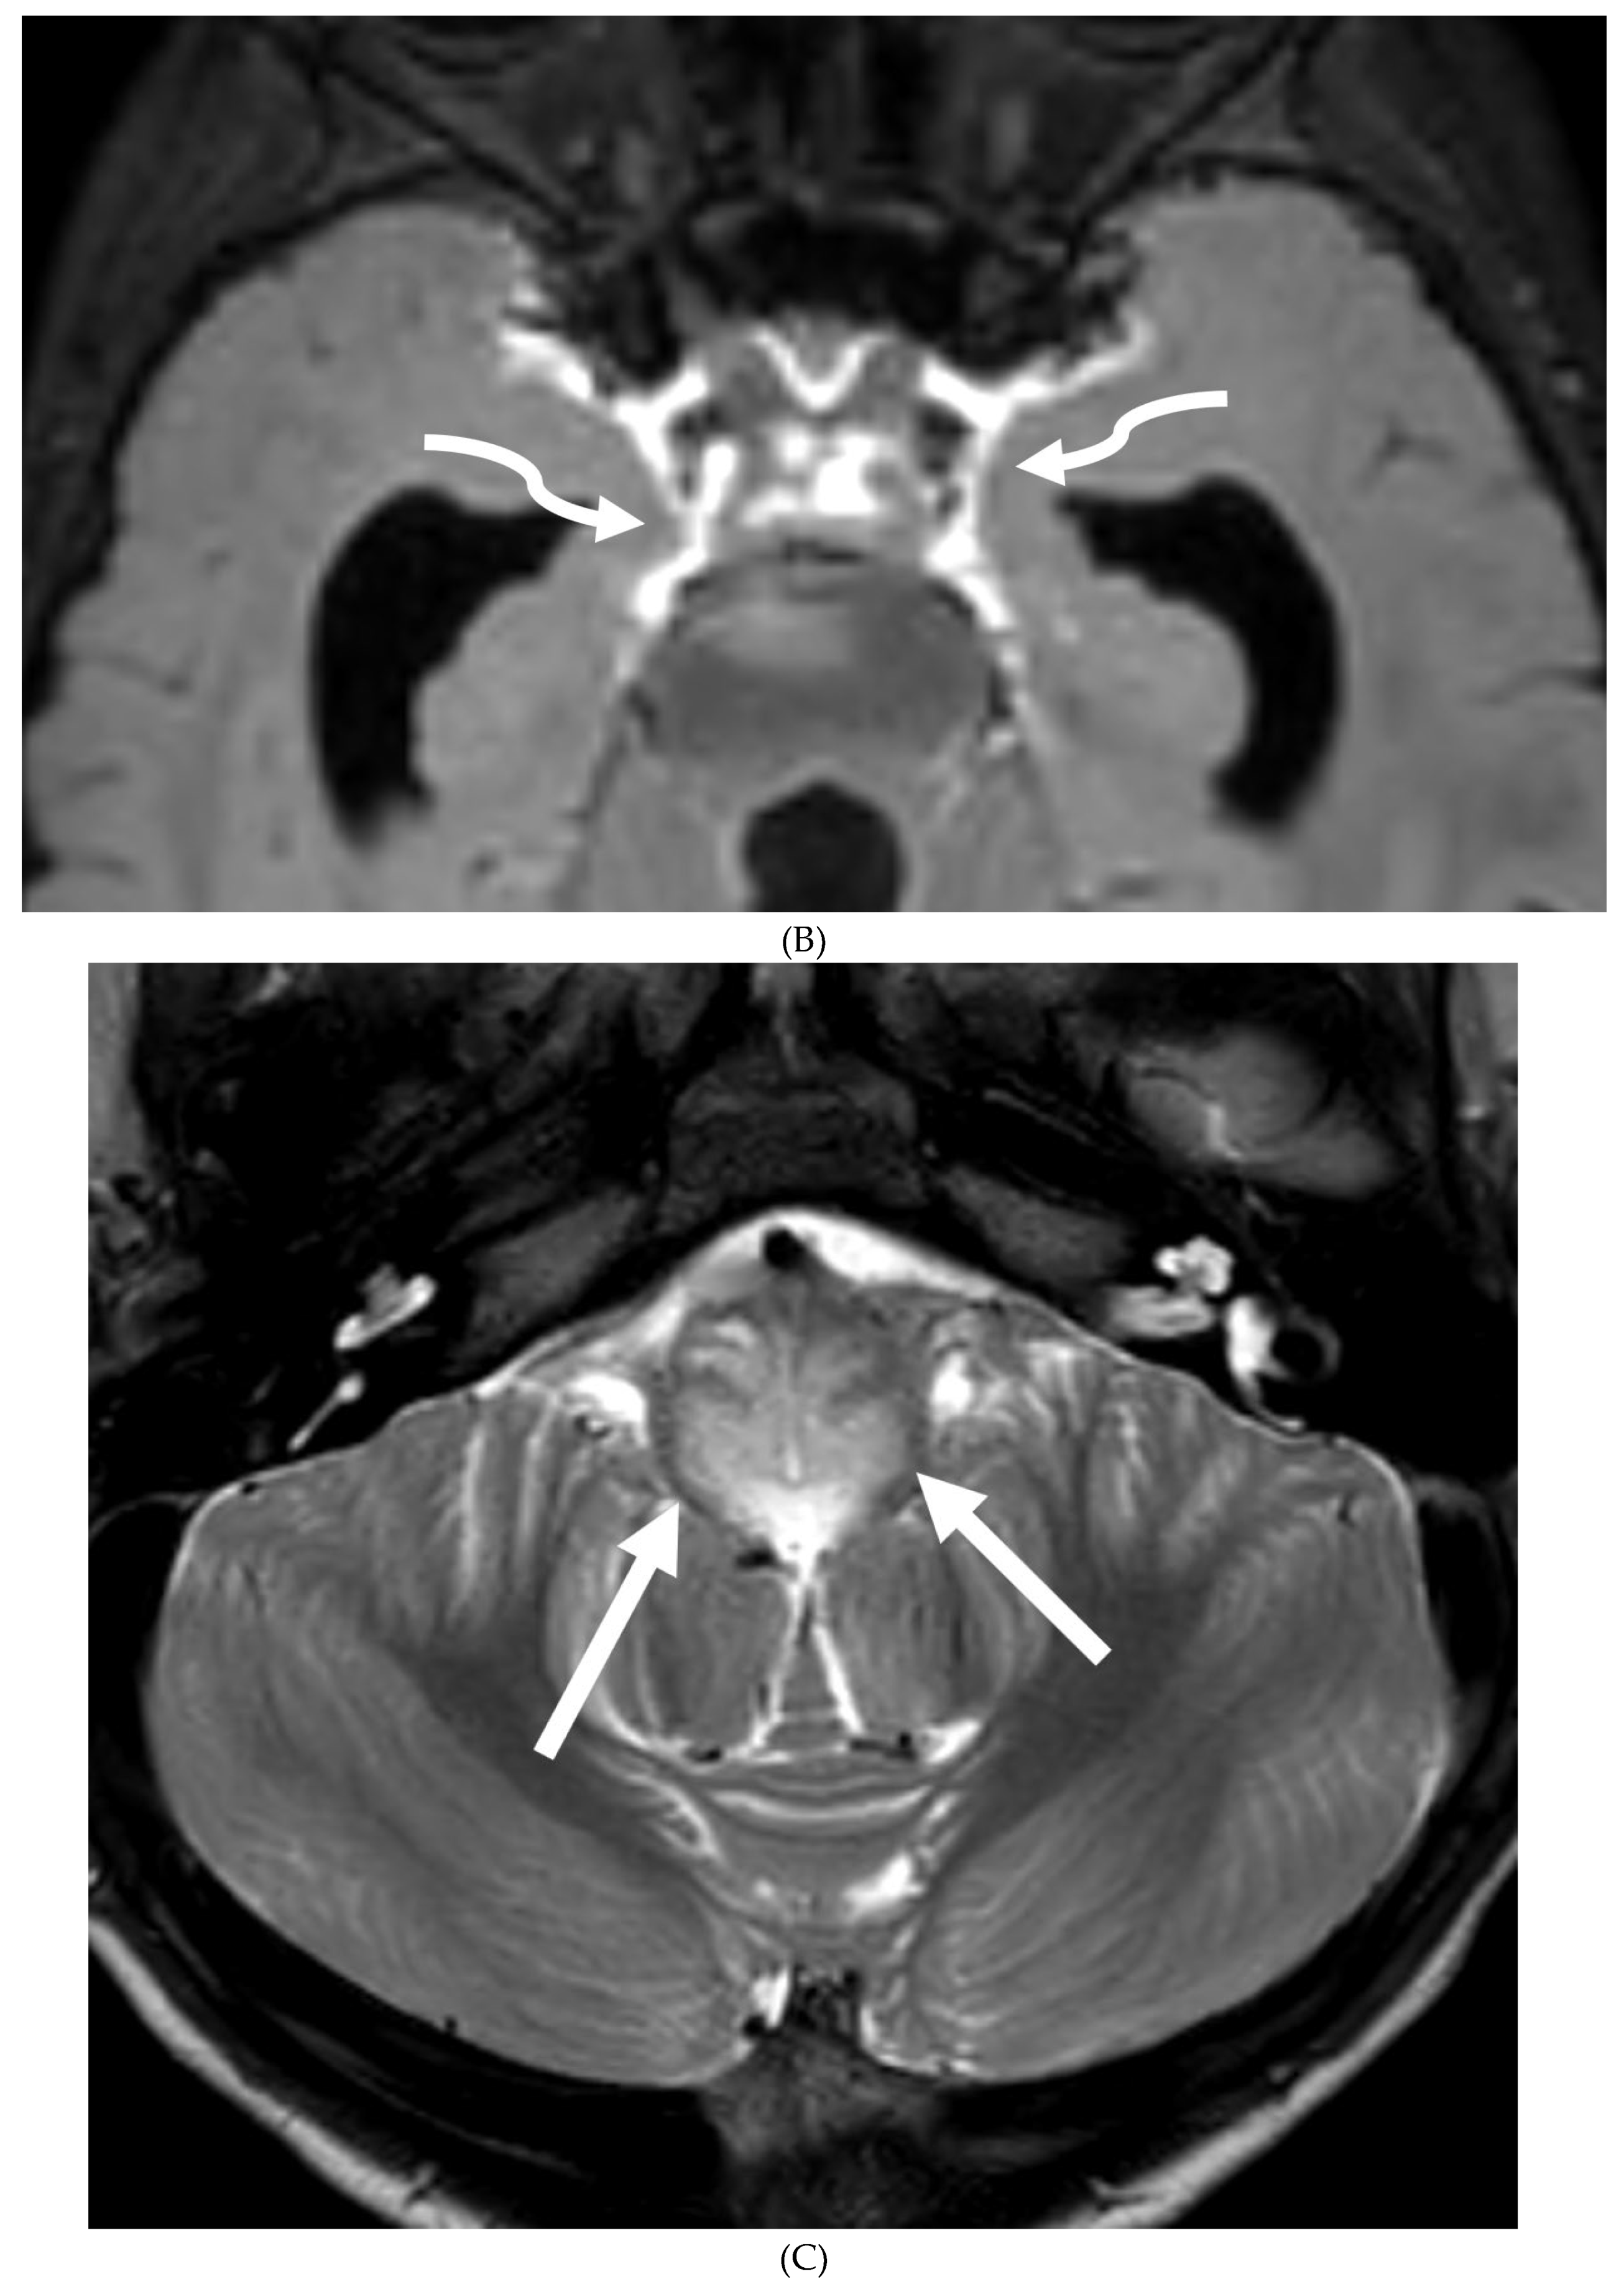

GUILLAIN BARRE SYNDROME

- Alkan O, Yildirim T, Tokmak N, Tan M. Spinal MRI findings of guillain-barré syndrome. J Radiol Case Rep. 2009;3(3):25-8. Epub 2009 Mar 1. PMID: 22470650; PMCID: PMC3303301. [CrossRef]

- Zuccoli G, Panigrahy A, Bailey A, Fitz C. Redefining the Guillain-Barré spectrum in children: neuroimaging findings of cranial nerve involvement. AJNR Am J Neuroradiol. 2011 Apr;32(4):639-42. Epub 2011 Feb 3. PMID: 21292802; PMCID: PMC7965877. [CrossRef]

- Yikilmaz A, Doganay S, Gumus H, Per H, Kumandas S, Coskun A. Magnetic resonance imaging of childhood Guillain-Barre syndrome. Childs Nerv Syst. 2010 Aug;26(8):1103-8. Epub 2010 Jun 17. PMID: 20556395. [CrossRef]

- Byun WM, Park WK, Park BH, Ahn SH, Hwang MS, Chang JC. Guillain-Barré syndrome: MR imaging findings of the spine in eight patients. Radiology. 1998 Jul;208(1):137-41. PMID: 9646804. [CrossRef]